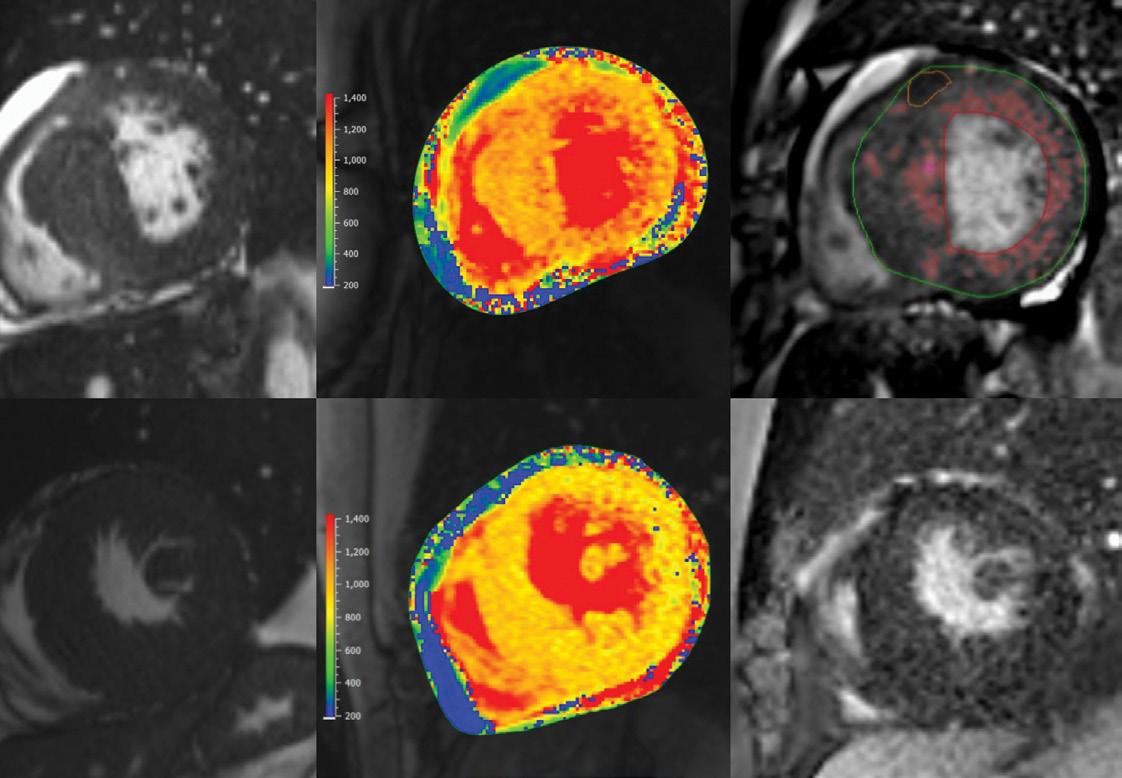

A comprehensive multi-parametric CMR examination allows for confirmation of HCM, characterization of morphology and severity of hypertrophy, assessment of LV function, exclusion of phenocopies, and information for SCD risk stratification. The protocol must include imaging with gadolinium contrast media. CMR cine imaging improves detection of hypertrophied segments and allows accurate measurement of wall thickness. T1-mapping has emerged as a valuable tool for myocardial tissue characterization which helps differentiate HCM, CA and FD (Figure 1). Late gadolinium enhancement (LGE) imaging allows detection of interstitial fibrosis (Also

Figure 1: Representative end-diastolic cine (left column), native-T1 mapping (middle column) and LGE images (right column) of cardiac amyloidosis (CA) (top row), HCM (middle row) and FD (bottom row), CA and HCM LGE images illustrate how LGE burden is calculated as a percentage of the myocardial mass. Native T1 relaxation times derived from T1 maps help differentiate these entities. In FD, the T1 relaxation time is shortened, whereas in CA, relaxation times are exceptionally long relative to normal myocardium.

BASELINE

10-YEAR FOLLOW-UP

Figure 1). CMR markers associated with increased risk of SCD that inform recommendation for a primary prevention implantable cardiac defibrillator (ICD) include myocardial wall thickness ≥ 30 mm, LV ejection fraction <50%, an apical aneurysm and/or LGE burden ≥15% of the left ventricular mass. Assessment of flow helps characterize location of LVOTO by differentiating flow acceleration due to SAM from nonHCM mechanisms.

Surveillance CMR is recommended every 3-5 years in those who initially do not meet criteria for primary prevention ICD but have potential to progress and may warrant ICD in the future. Figure 2 illustrates the progression of apical hypertrophy to apical aneurysm in a 10-year followup period. Surveillance ECG may provide clues that myocardial changes

are taking place. Note the loss of QRS and T-wave voltage on ECG across the same monitoring period.

Figure 2. HCM changes over time. This example illustrates apical variant HCM that progressed to apical aneurysm over a 10-year follow-up period. Note that surveillance ECG can provide clues to myocardial changes. In this case a significant decrease in QRS and T-wave voltage was observed across all ECG leads.